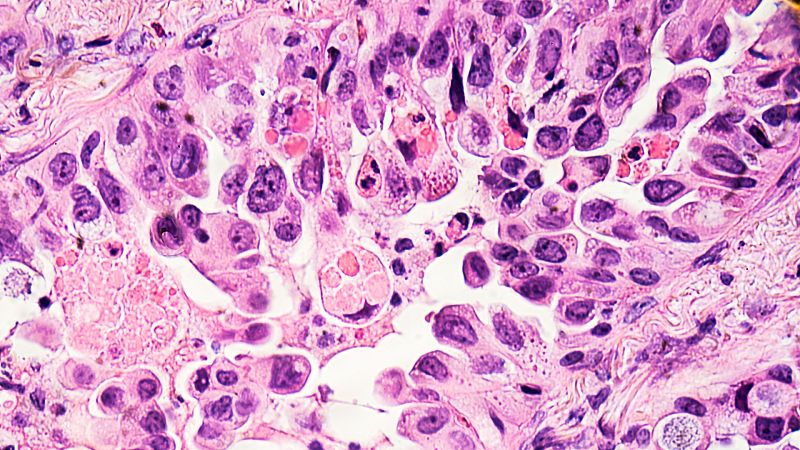

Foto: Recreación 3D de células cancerígenas (Getty Images)